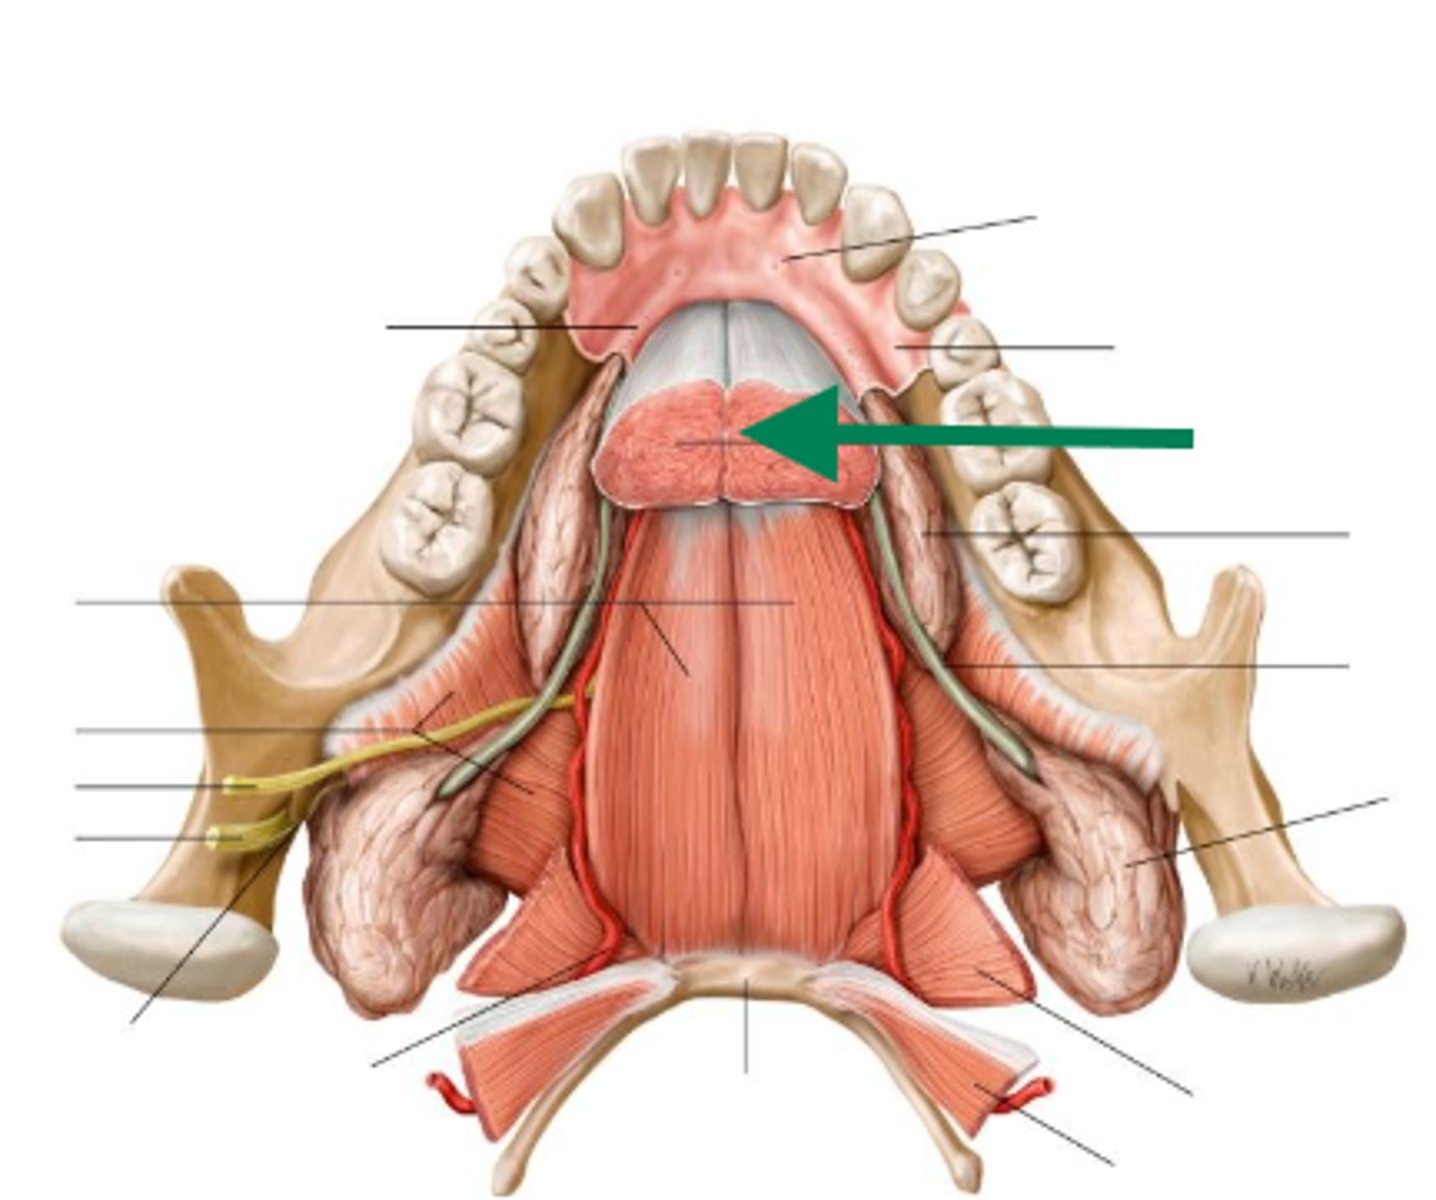

genioglossus

geniohyoid

lingual nerve

lingual artery

lingual vein

lingual nerve

genioglossus

geniohyoid

mylohyoid

lingual artery

lingual nerve